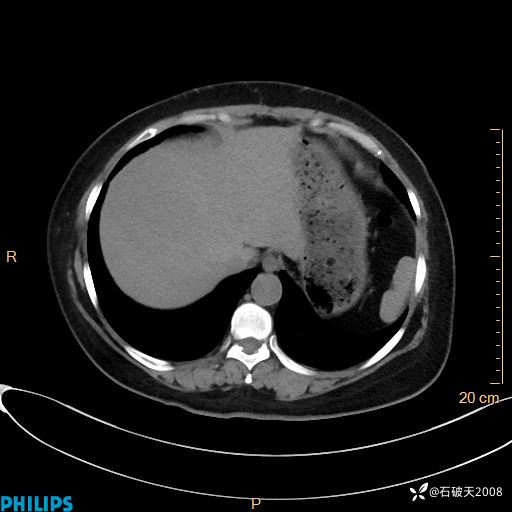

肺窗